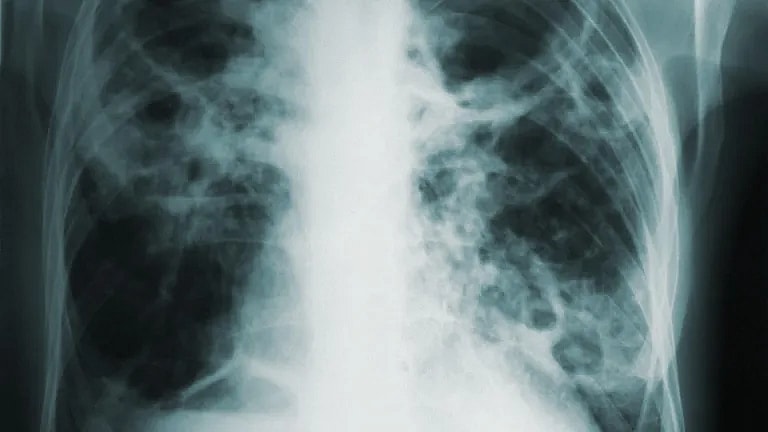

What is Pulmonary lobectomy: Overview, Benefits, and Expected Results